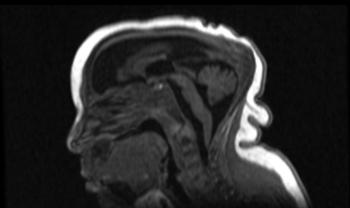

Another study analyzed the imaging results of three target groups affected by Zika: adults who developed acute neurological syndrome, newborns with vertical infection with neurological disorders, and pregnant women with rash outbreaks suggestive of Zika.

Many of the adults had symptoms of Guillain-Barré syndrome, a rare disorder in which the body's immune system attacks the nervous system causing rapid onset muscle weakness. A few showed inflammation of the brain and spinal cord (Bickerstaff's encephalitis) or brain stem and spinal cord lesions. Common MRI findings included enhancement of certain spinal and facial nerves. In the newborns, MRI showed orbital injuries and anatomical changes in brain tissue.

"It was alarming to find so many cases of neurological syndromes in adults, some very serious, related to Zika virus infection," said study author Emerson de Melo Casagrande, M.D., from the Department of Radiology at Antonio Pedro University Hospital - Federal Fluminense University. "We have also noticed a difference between these syndromes, even though the trigger was the same."